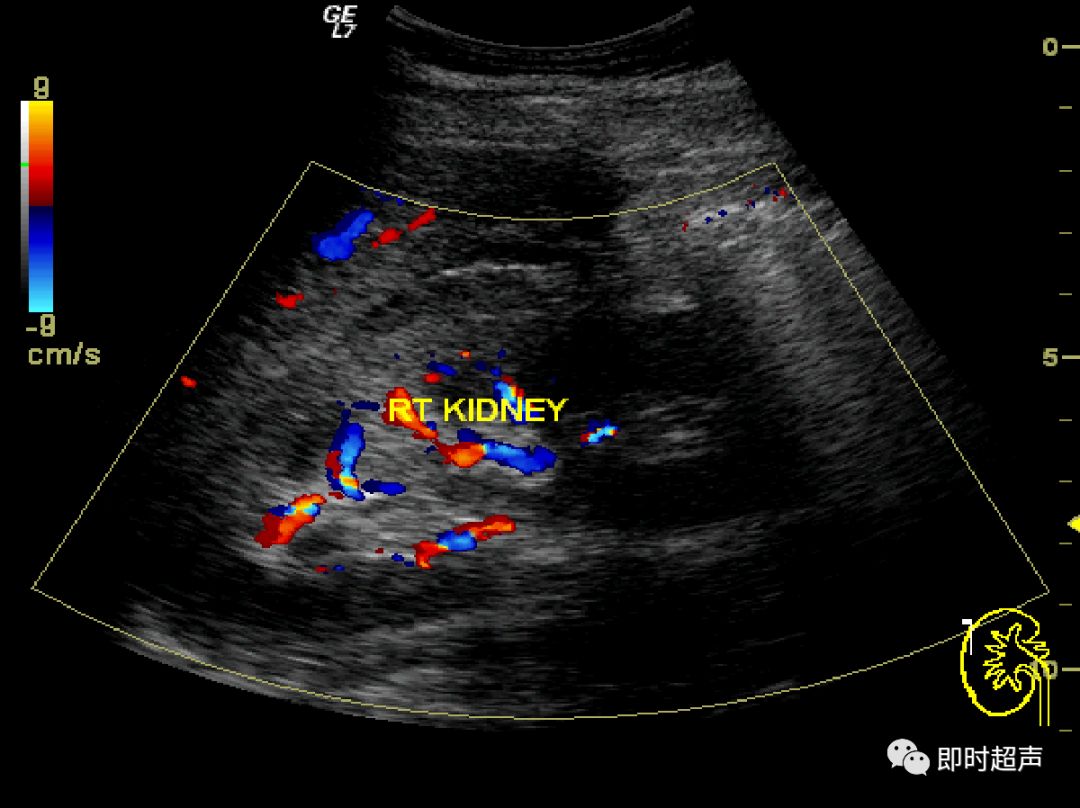

内脏反转超声报告

内脏反转超声报告,内脏反位超声报告模板